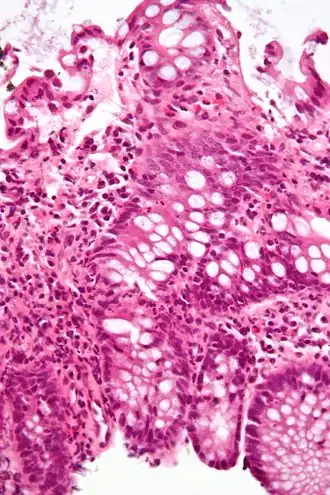

Colitis

Colitis is de algemene benaming voor een ontsteking van de dikke darm (colon).

Colitis wordt gekenmerkt door lichte tot hevige diarree met bloedverlies gepaard gaand met koorts en buikpijn. De diagnose wordt doorgaans gesteld na onderzoek met een endoscoop.